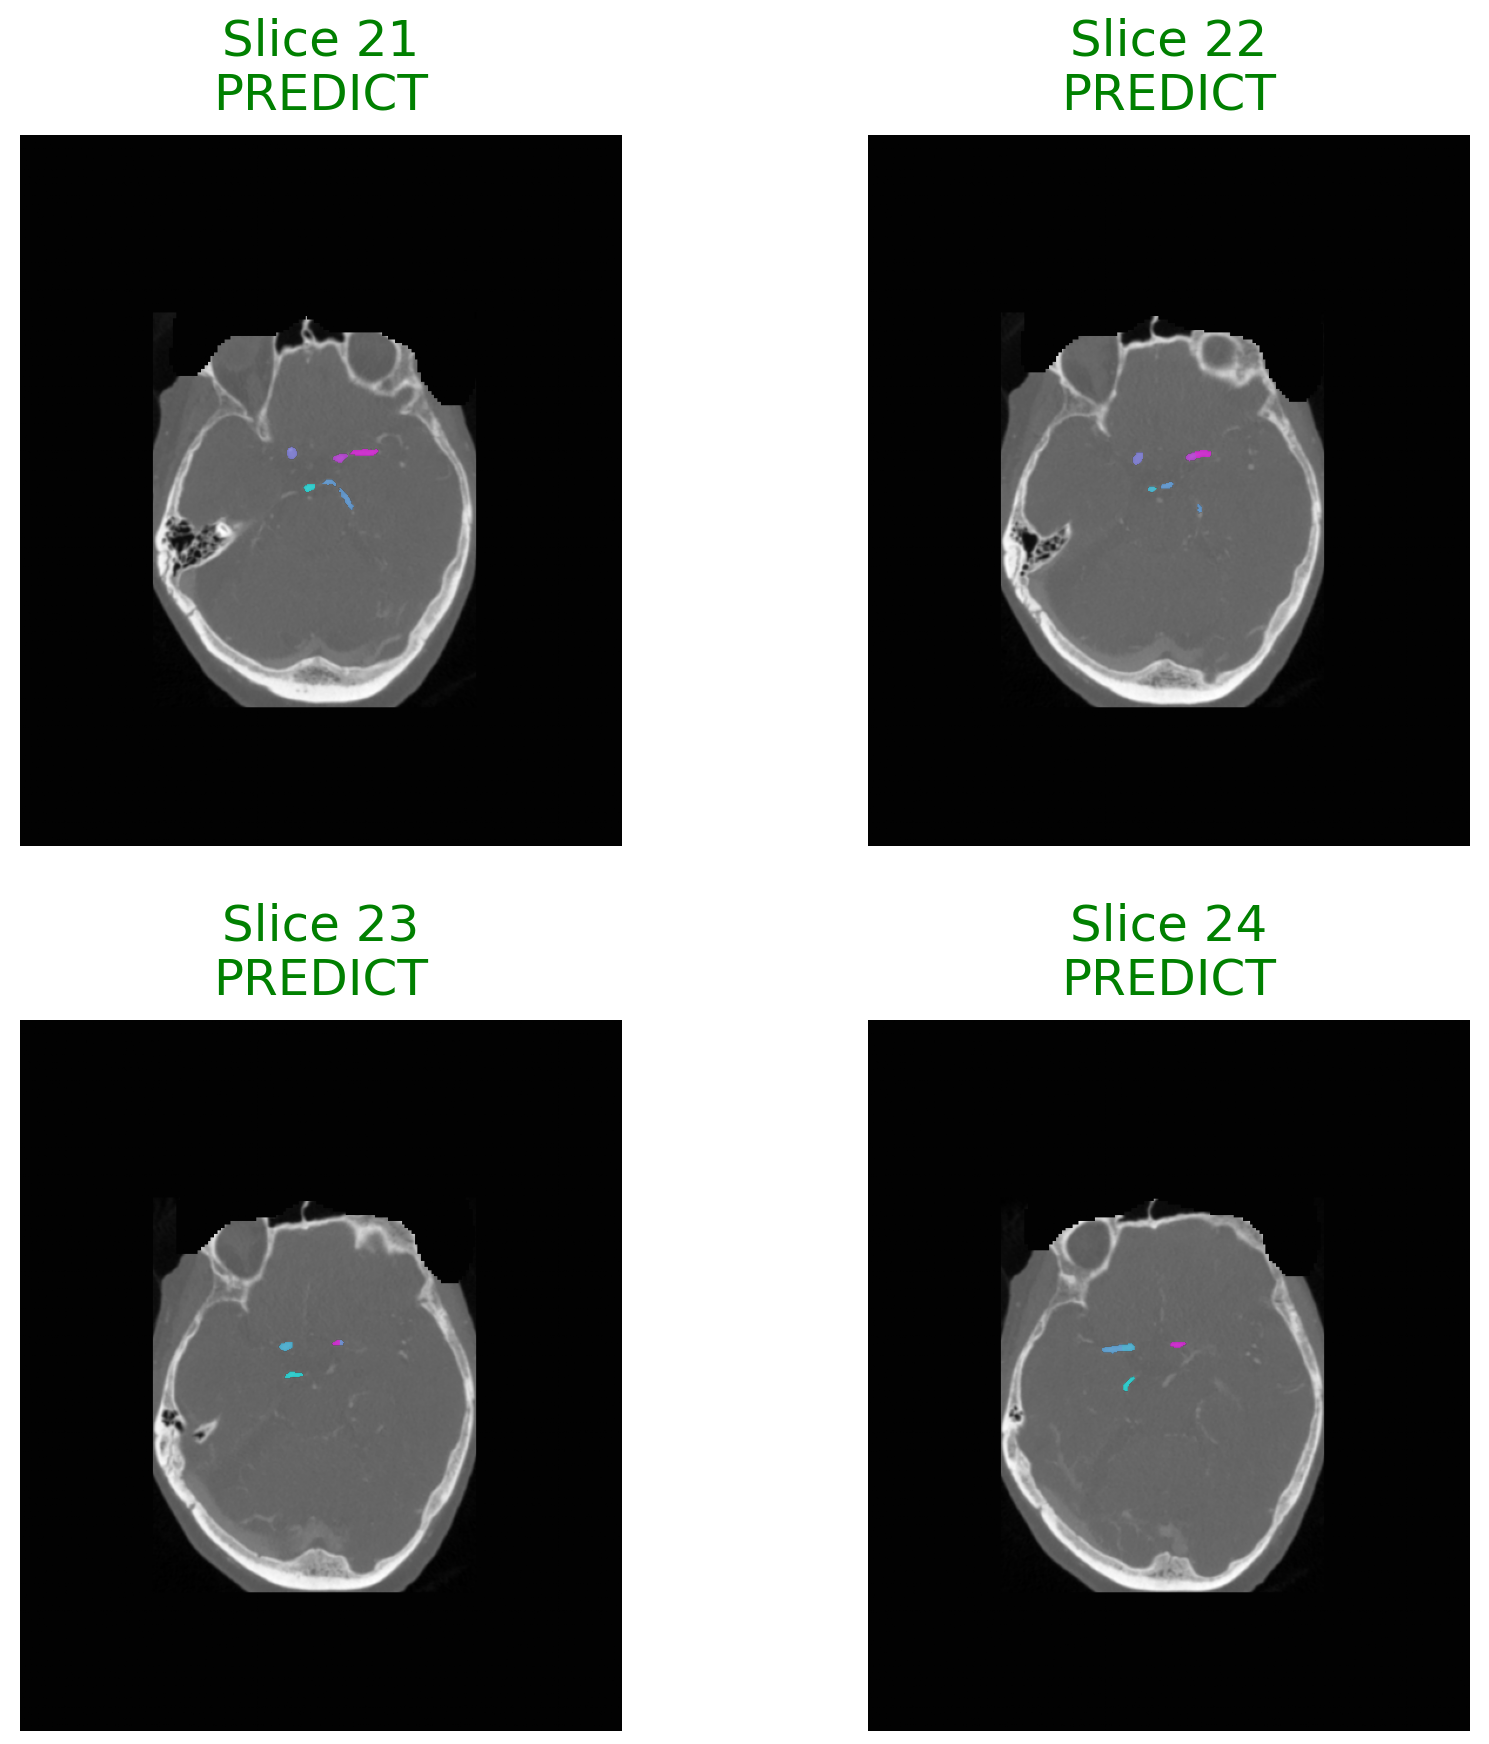

Figure 3 Samples illustrate the difference of predicting and not-predicting outcomes within individual image slices. Sections with clearly defined lesion characteristics are associated with high confidence decisions, meanwhile abstention takes place in regions of uncertainty and misdiagnosis.

Refer to caption

Figure 3: The visualization of decision outcomes influenced by uncertainty across representative image slices. Slices characterized by low uncertainty result in confident predictions, whereas those with high uncertainty necessitate abstention and referral to a clinician.

Figure 4: visualizing decision outcomes influenced by uncertainty on axial brain slices, we gain a deeper understanding of system behavior. In diagnostically clear sections, confident predictions are made, whereas in adjacent or ambiguous areas, abstention occurs, mirroring clinically appropriate deferral behavior.

Figure 4 The summary of the text encompasses two predictions and abstentions concerning axial slices. The model’s interpretability indicates that confident predictions are made on slices exhibiting localized lesion structures, whereas abstentions predominantly occur in slices with low contrast, limited diagnostic cues, or ambiguous anatomical locations.